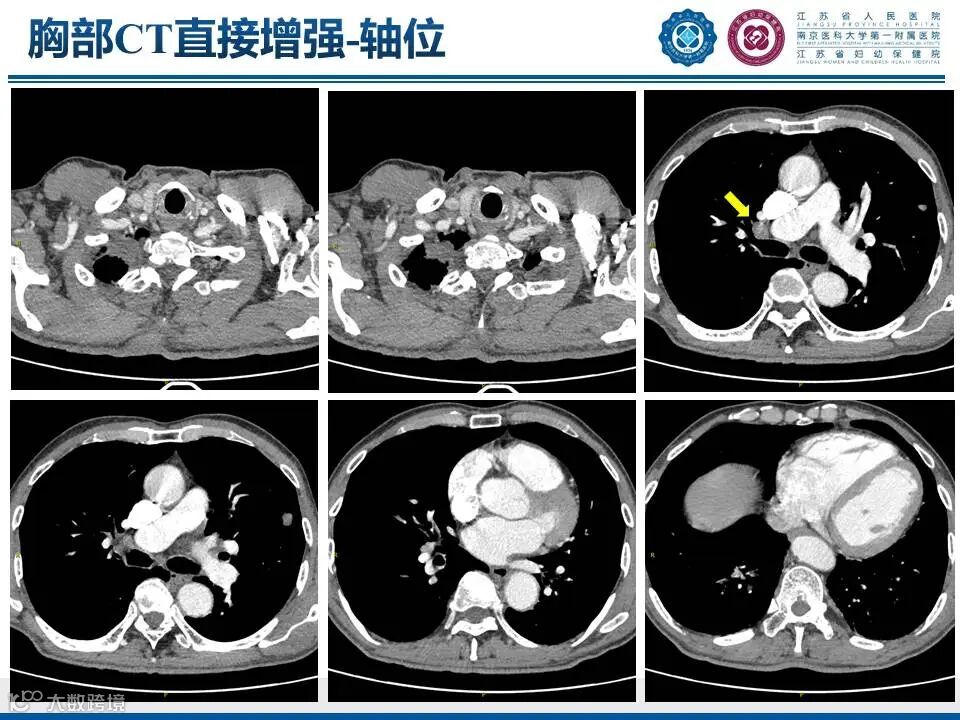

肺上沟瘤

——肩痛背后的致命危机